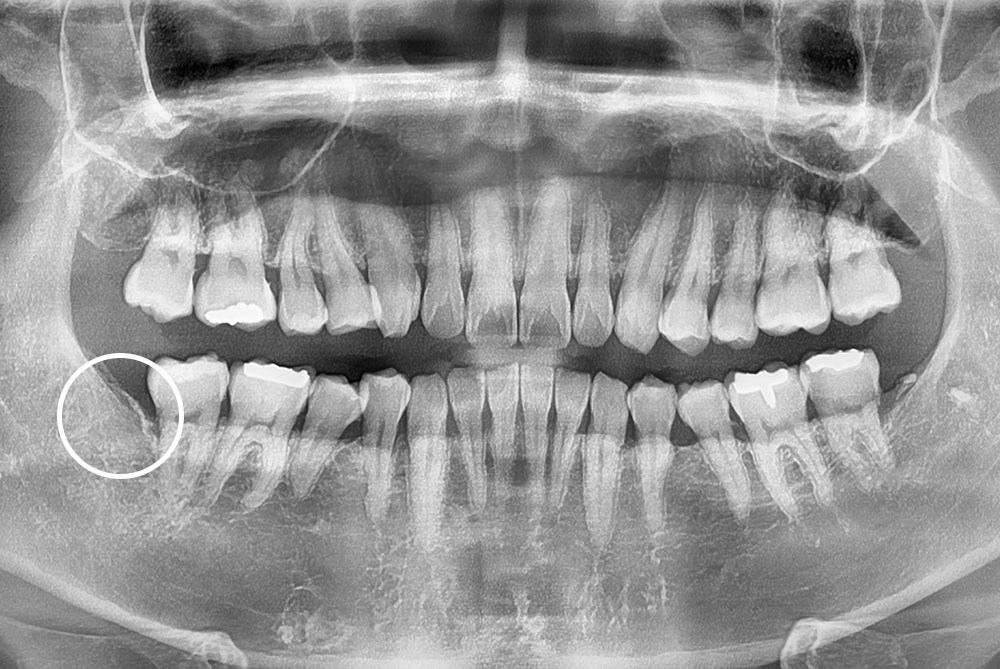

[사랑니] 매복 사랑니 발치

치료전 : 2019-07-10